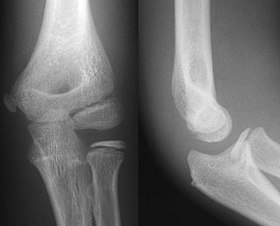

This thesis works to address a pivotal challenge in medical image analysis: the reliance on extensive labeled datasets, which are often limited due to the need for expert annotation and constrained by privacy and legal issues. By focusing on the development of self-supervised learning techniques and domain adaptation methods, this research aims to circumvent these limitations, presenting a novel approach to enhance the utility and efficacy of deep learning in medical imaging. Central to this thesis is the development of the Medformer, an innovative neural network architecture designed for multitask learning and deep domain adaptation. This model is adept at pre-training on diverse medical image datasets, handling varying sizes and modalities, and is equipped with a dynamic input-output adaptation mechanism. This enables efficient processing and integration of a wide range of medical image types, from 2D X-rays to complex 3D MRIs, thus mitigating the dependency on large labeled datasets. Further, the thesis explores the current state of self-supervised learning in medical imaging. It introduces novel pretext tasks that are capable of extracting meaningful information from unlabeled data, significantly advancing the model's interpretative abilities. This approach is validated through rigorous experimentation, including the use of the MedMNIST dataset, demonstrating the model's proficiency in learning generalized features applicable to various downstream tasks. In summary, this thesis contributes to the advancement of medical image analysis by offering a scalable, adaptable framework that reduces reliance on labeled data. It paves the way for more accurate, efficient diagnostic tools in healthcare, signifying a major step forward in the application of deep learning in medical imaging.💡 Deep Analysis